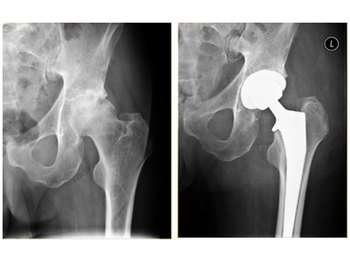

The acetabulum (cup) and the femur head (the ball) are cut and replaced with various combinations of metal/plastic/ceramic implants (stems and cups) and fixed with or without cement depending on the age of patient and quality of bone.